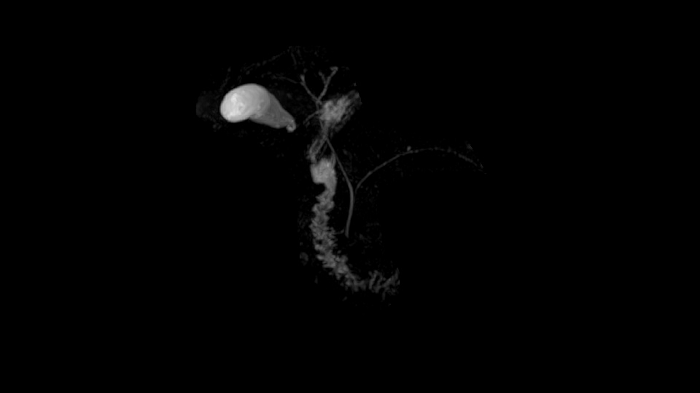

Abdomen

MRCP with Compressed Sensing

Abdominal imaging with T2w SPACE of the biliary ducts can be expedited with Compressed Sensing to reduce acquisition times. Both techniques offer high-resolution, high-quality MRCP for uncompromised abdominal investigation.

Compressed Sensing factor 6.5 | 1.2 x 1.2 x 1.0 mm3 | TA = 4:21 minutes

- Contour L Coil

- Spine Coil

Image Courtesy: University Hospital Erlangen, Germany | Image-ID: 4aaaa0465